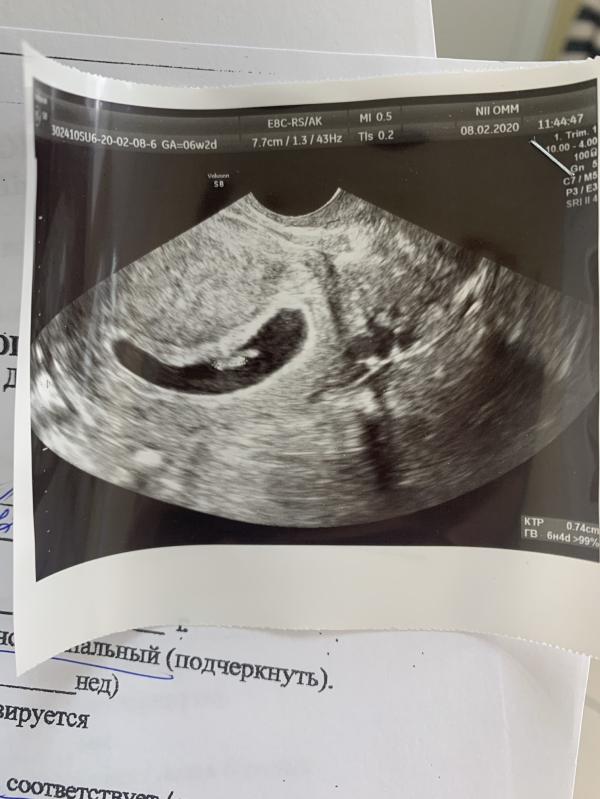

Первое узи 6-7 недель ( третья беременность , - резус фактор )

Сегодня сходила на первое узи для постановки на учёт . Эмбрион увидели , сердцебиение послушали .

@anytttaa 0.60см ктр по акушерскому сроку 7 нед 3 дня.а по плоду 6-7нед.странно у вас больше ктр. От чего это зависит?срок то одинаковый с вами.